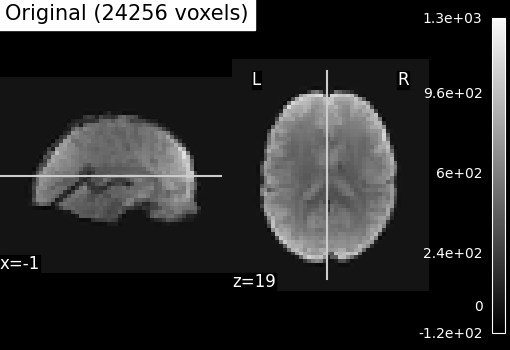

Compressed representation of Ward clustering¶

Second, we illustrate the effect that the clustering has on the signal. We show the original data, and the approximation provided by the clustering by averaging the signal on each parcel.

plotting.plot_epi(

title=f"Original ({int(original_voxels)} voxels)",

# As you can see below, this approximation is almost good, although there

# are only 2000 parcels, instead of the original 60000 voxels